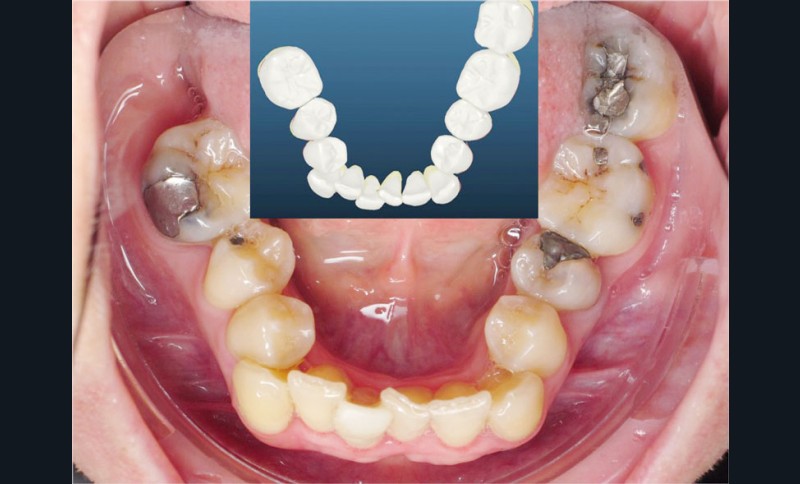

Un appareillage Damon métal a été mis en place, réalisé à partir d’un set up numérique Insignia pour obtenir un contrôle précis des torques et de la forme d’arcade et réduire le temps de finition grâce à un collage indirect très précis.

De larges surélévations postérieures étalées ont été mises en place et la patiente a porté des élastiques précoces suivant les principes de la technique Damon. Les 14 et 24 rempliront le rôle des 13 et 23.

L’objectif, en utilisant la technique Insignia est de réduire le temps de traitement de 28 à 18 mois avec 12 rendez-vous (fig. 5 à 14).